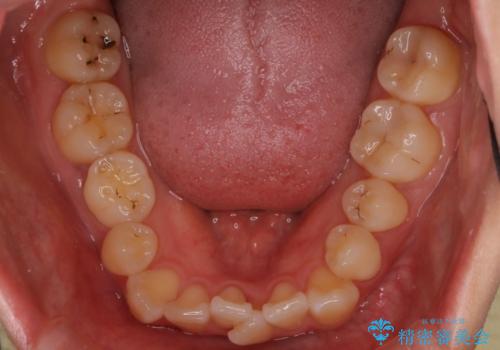

- 患者様は、右下第2小臼歯(5番)の先天欠如により乳歯が残存している状態でした。

加えて、**下顎前歯部に叢生(歯のがたつき)**が見られ、審美的・機能的な改善を希望されて来院されました。

診査の結果、乳歯は長期間機能していましたが、将来的な脱落のリスクが高く、インプラントによる永久歯の補綴が望ましいと判断しました。

また、欠損部にインプラントを埋入するには、前後の歯の傾斜改善とスペース確保のための矯正治療が必要でした。

下顎前歯の叢生も同時に改善できるよう、全体的なワイヤー矯正による治療計画を立案しました。

下顎前歯の叢生が整い、右下5番部には機能的かつ審美的なインプラント補綴が完了しました。

咬合全体のバランスも改善し、長期的な安定性が期待される状態となりました。